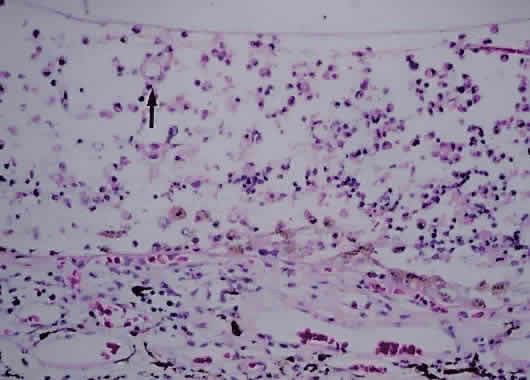

PROGRESSIVE OUTER RETINAL NECROSIS. Descriptively named, progressive outer retinal necrosis is a progressive, multifocal, necrotizing inflammation of the outer retina. Unlike CMV retinitis, it is not associated with significant retinal vasculitis. Caused by the varicella zoster virus, it often follows an episode of cutaneous zoster.108 Rutzen and associates109 reported the histopathology from two cases of progressive outer retinal necrosis requiring retinal biopsy. Retinal necrosis was present in one, with the other showing only retinal atrophy (Fig. 12). Both revealed herpes group viral DNA. Unlike the typical occlusive vasculitis seen in CMV retinitis, retinal vessels were patent in the case with retinal necrosis.

Fig. 12. Photomicrograph of retina from a patient with progressive outer retinal necrosis showing loss of normal retina architecture but preservation of retinal vessels (arrow) (hematoxylin and eosin; × 200).